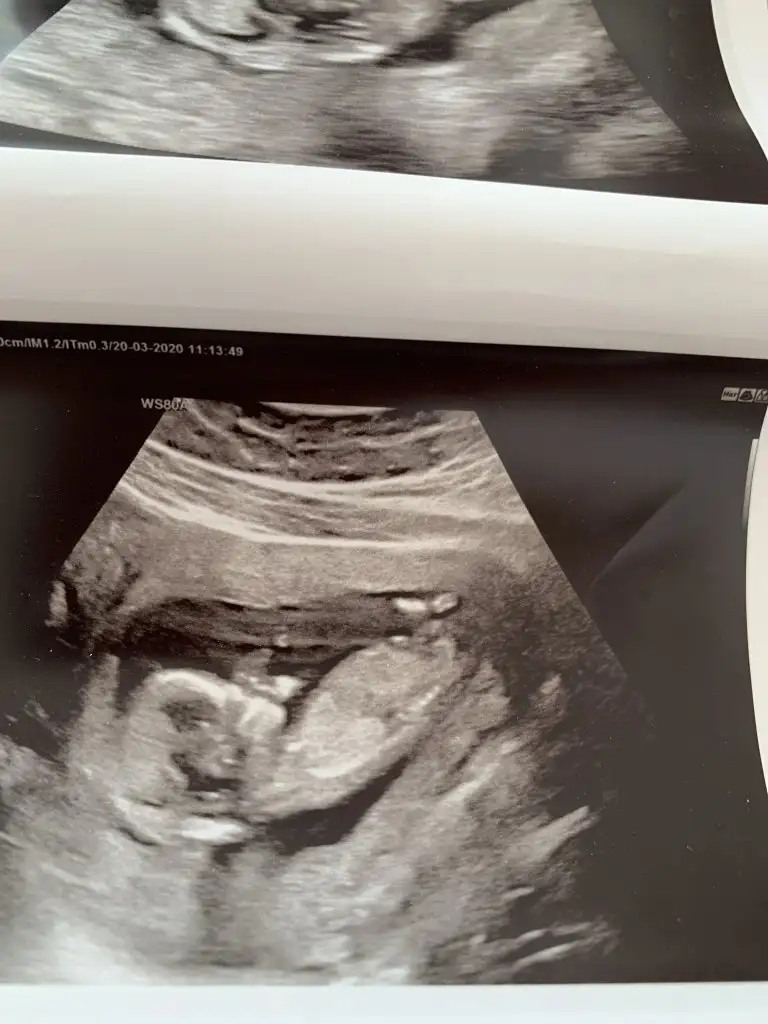

Merhaba hanimlar ben yeni kayit oldum burada bebegim 13 haftalik bi tahmin yapa bilir misiniz lutfen

Nubu net değil başka usg varsa paylaşın sanki emin değilim kız gibi gibi eminde değilim vaşka usgde teyit ederim 😉

Ben hiç anlamıyorum doktorum söylemedi anlayan varsa yazabilir mi ??